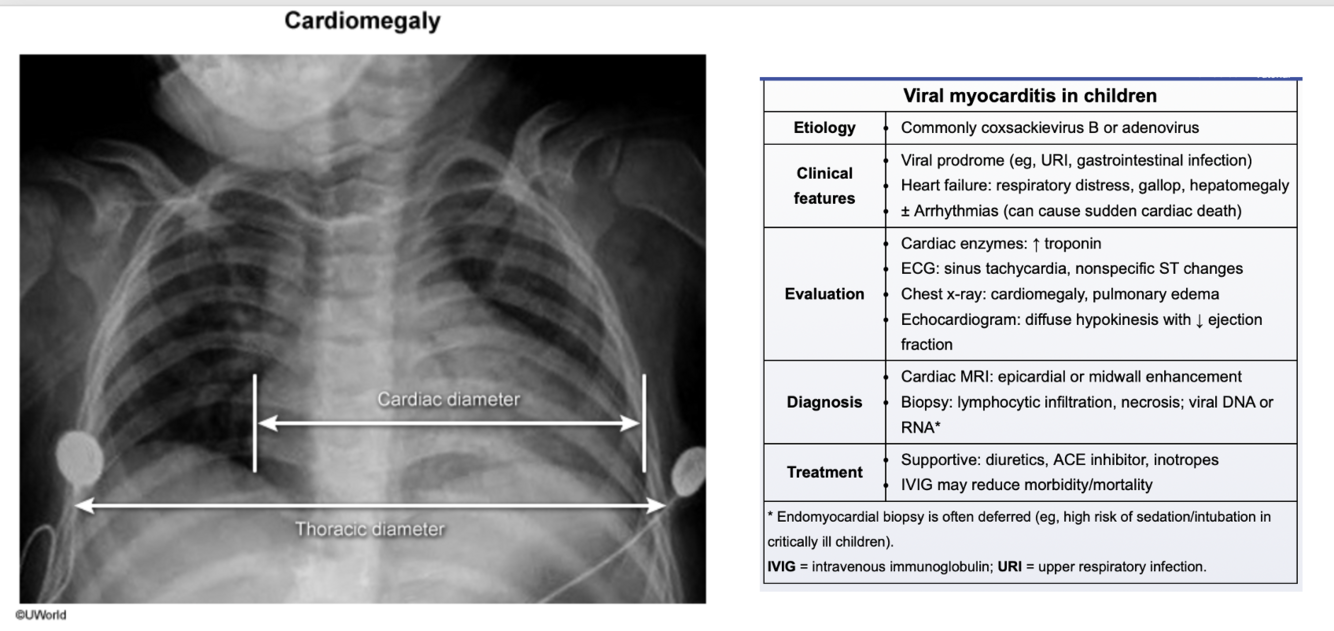

A viral prodrome often precedes the illness, seen with fever, rhinorrhea, congestion, and cervical lymphadenopathy. Patients then typically develop fatigue, tachycardia, and respiratory distress (eg, retractions, nasal flaring, tachypnea, crackles) with hypoxemia from acute left-sided heart failure and pulmonary edema. Because symptoms overlap with common viral illnesses, the diagnosis is challenging and may be delayed. However, progressive symptoms leading to dilated cardiomyopathy with secondary mitral regurgitation can cause an S3 gallop and holosystolic murmur, as seen here. Reduced cardiac output can lead to hypotension, decreased peripheral pulses, and oliguria; hepatomegaly can also occur due to passive congestion from right-sided heart failure. Initial workup includes cardiac enzymes, ECG, chest x-ray, and echocardiogram. Chest x-ray reveals cardiomegaly (cardiothoracic ratio >50% and bilateral hazy opacities (pulmonary edema). Echocardiogram often shows diffuse hypokinesis with decreased ejection fraction. Endomyocardial biopsy or cardiac MRI is needed to confirm the diagnosis, but treatment (eg, diuretics) is often initiated based on clinical suspicion.

Viral infections, particularly Coxsackie B virus, adenovirus, and parvovirus B19.

CXR can be used initially. Cardiac MRI, which shows myocardial edema and late gadolinium enhancement would be used in the confirmatory stages when establishing a diagnosis.